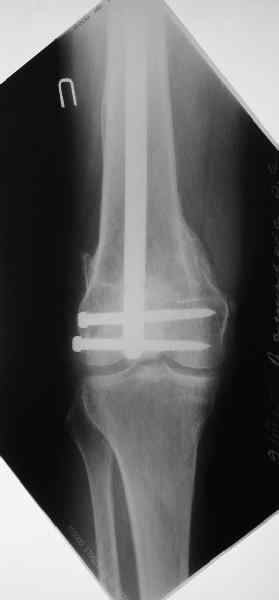

Это результат через полгода. К сожалению, пациент больше не приезжал на контрольный осмотр.

Чтобы больной не смог сгибать колено, выстоять в сустав железо должно побольше значительно, чем на 1 мм. В приложении снимок с выстоянием ммм на 3, видна и функция колена. Хотя клиника импинджмента была, но даже не на один восклицательный знак. После удаления стержня проблемы и вовсе рассосались.